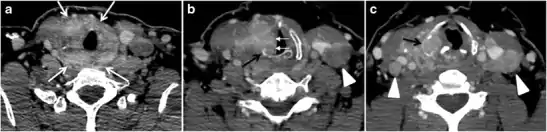

The radiologist must evaluate the central structures draping the thyroid gland including the trachea, oesophagus, larynx, and pharynx, as well as the recurrent laryngeal nerve. Invasion is suspected if the thyroid mass abuts the airway or oesophagus for more than 180 degrees. Luminal deformity, mucosal thickening and mucosal focal irregularity are more specific indicators of invasion. Obliteration of the fat planes of the tracheoesophageal groove in three axial images and signs of vocal cord paralysis are indicative of recurrent laryngeal nerve invasion. Invasion of these central structures meets the criteria for T4a disease (Figs. 5 and and6)6).[1]

Arterial invasion constitutes T4b disease, which may preclude curative surgery. More than 180 degrees of arterial encasement is suggestive of invasion, however, arterial deformity or narrowing is much more suspicious for invasion. The carotid artery is the most commonly involved artery; however, the mediastinal vessels should also be examined. Encasement of the carotid artery or mediastinal vessels for more than 270 degrees is unlikely to be resectable. On the other hand, occlusion or effacement of the internal jugular vein can occur without invasion and does not influence surgical resectability or staging. Asymmetry of the strap muscle and the tumour abutting its external surface are signs of an invasion. However, invasion of the pre-vertebral musculature is more challenging, as a large lesion can compress the muscle without invasion (Figs. 5 and and6)6).[1]

Fig. 6. A 61-year-old female patient with locally aggressive PTC. an Enhanced axial CT scan of the neck demonstrates a heterogeneous infiltrative thyroid mass. This mass diffusely involves the entire gland and circumferentially encases the trachea with involvement of bilateral tracheoesophageal grooves (white arrows). b, c Additional axial cranial images show right cricoid cartilage destruction (black arrows in b), right thyroid cartilage destruction (black arrow in c), right vocal cord paralysis (white arrows in b), and bilateral cervical lymphadenopathy (arrowheads).[1]